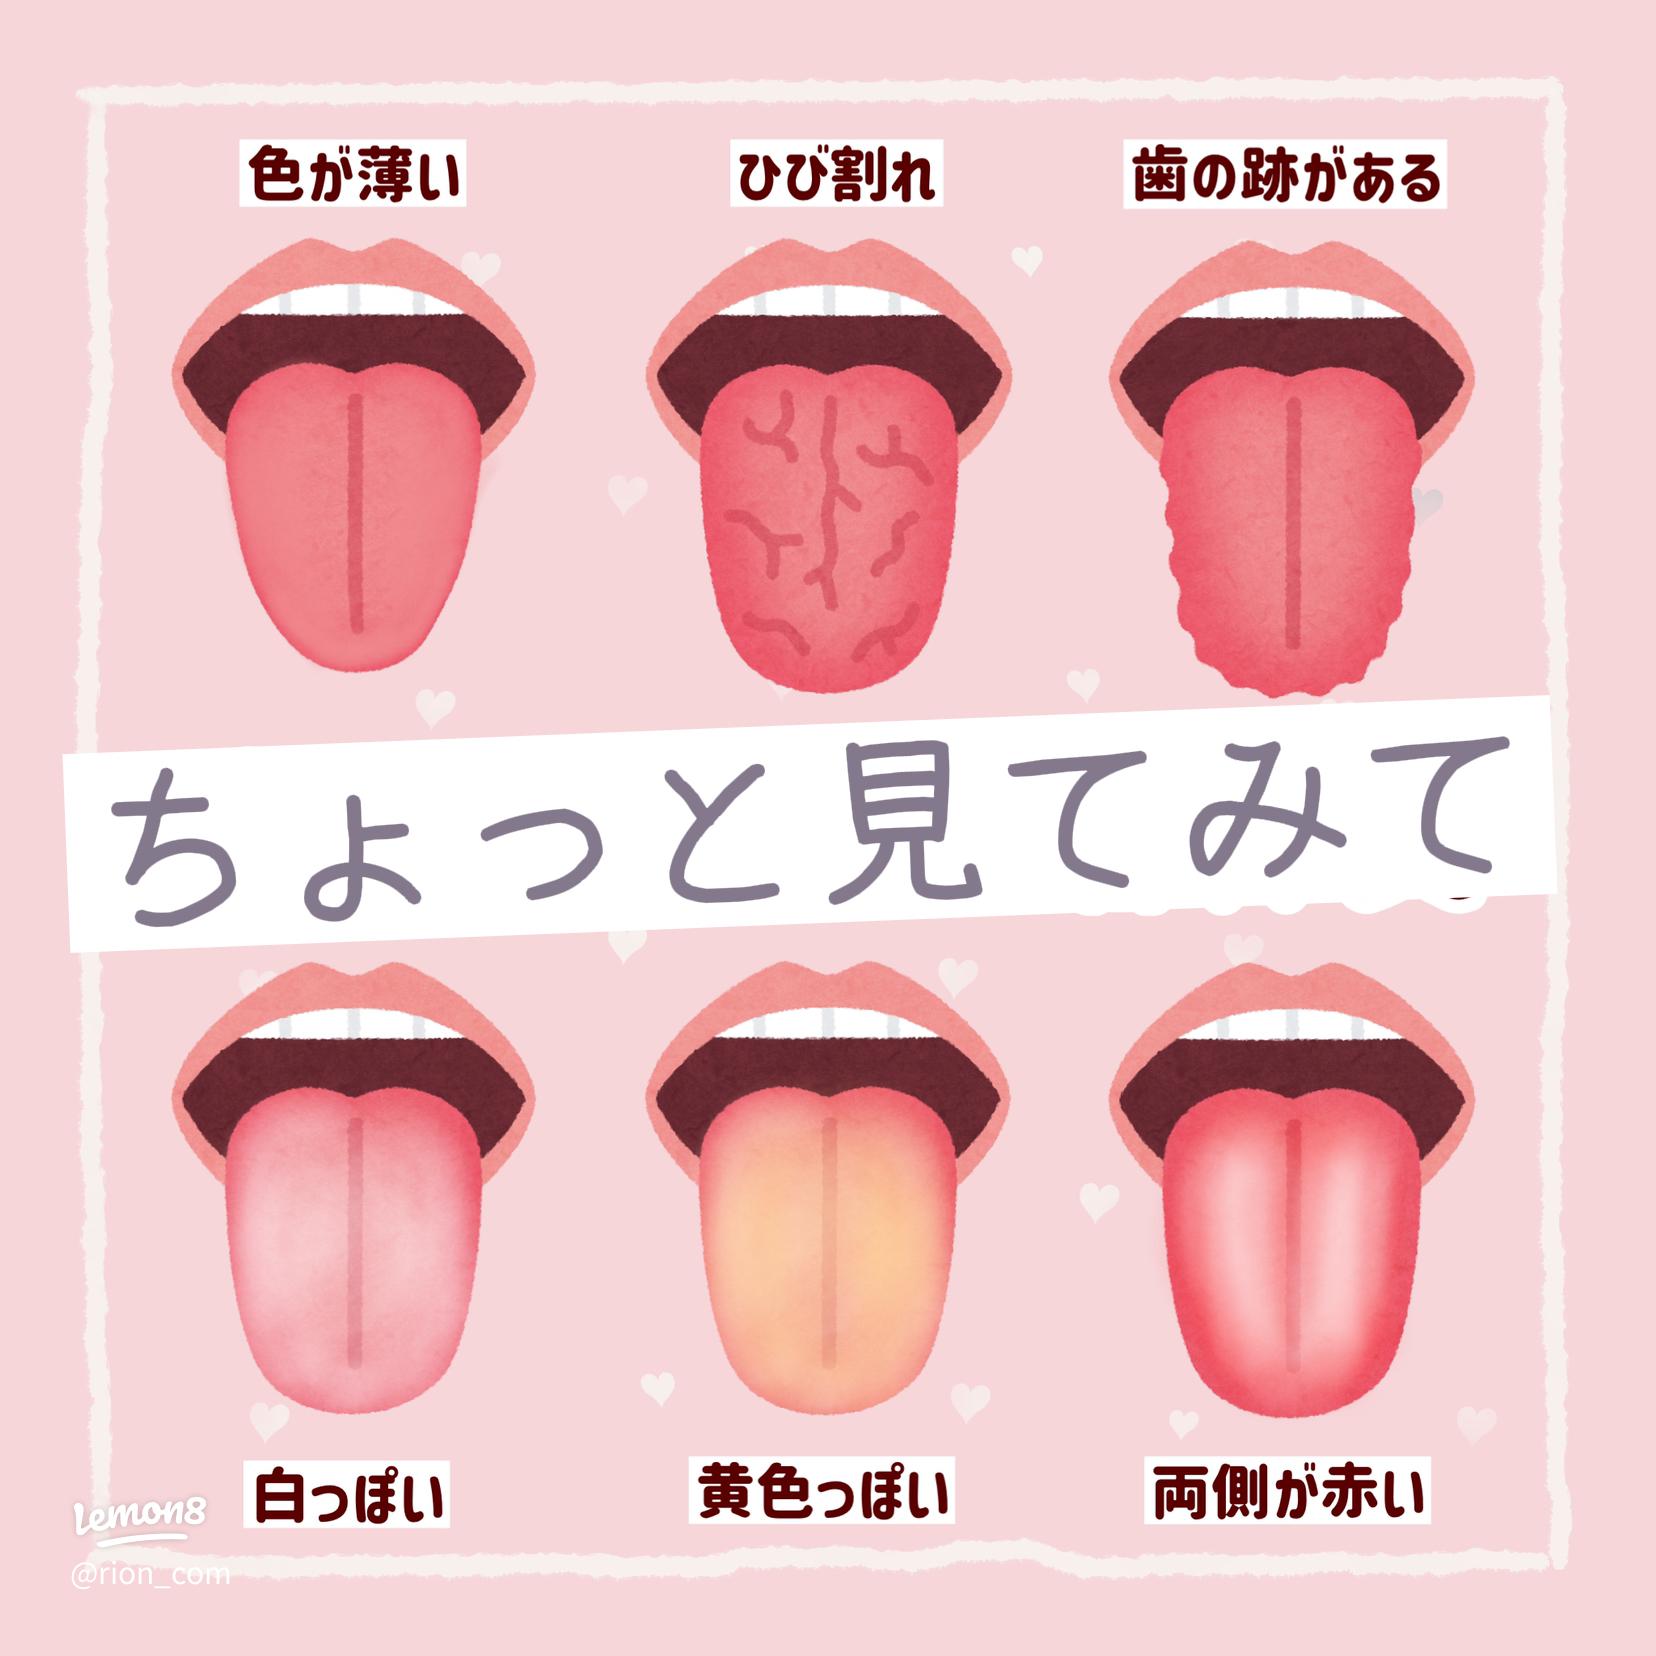

白い、ガタガタ、ひび割れ 。“舌”でわかる体調不良のサインとは?田中友也さん 季節の養生法からだにいいこと。

舌のサイン 院長ブログ八尾市のオカモト鍼灸整骨院。

舌診~毎日鏡の前で健康チェックをしたくなる舌の状態を解説 祥泉針灸整骨院。

舌で美容体質を知る方法2024 年のリアルなLemon8ユーザー体験。